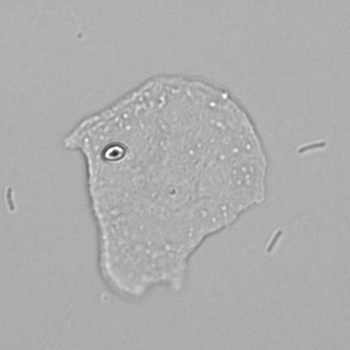

Squamous

In women, squamous epithelium is located at the base of the bladder and urethra, in men at the end of the urethra and foreskin. In addition, they line the inside of the vagina and perineum. Finding a small amount of squamous cells in urine is normal because these cells are constantly being renewed and replaced. Large amounts are usually caused by urine being collected after it has run down nearby areas such as the vagina, perineum or foreskin; this is referred to as contamination.

Sometimes these epithelial cells contain conspicuous dark granules; keratohyaline granules. These contain substances that contribute to the cornification of the skin layer. Their presence is normal and should not be confused with bacteria.